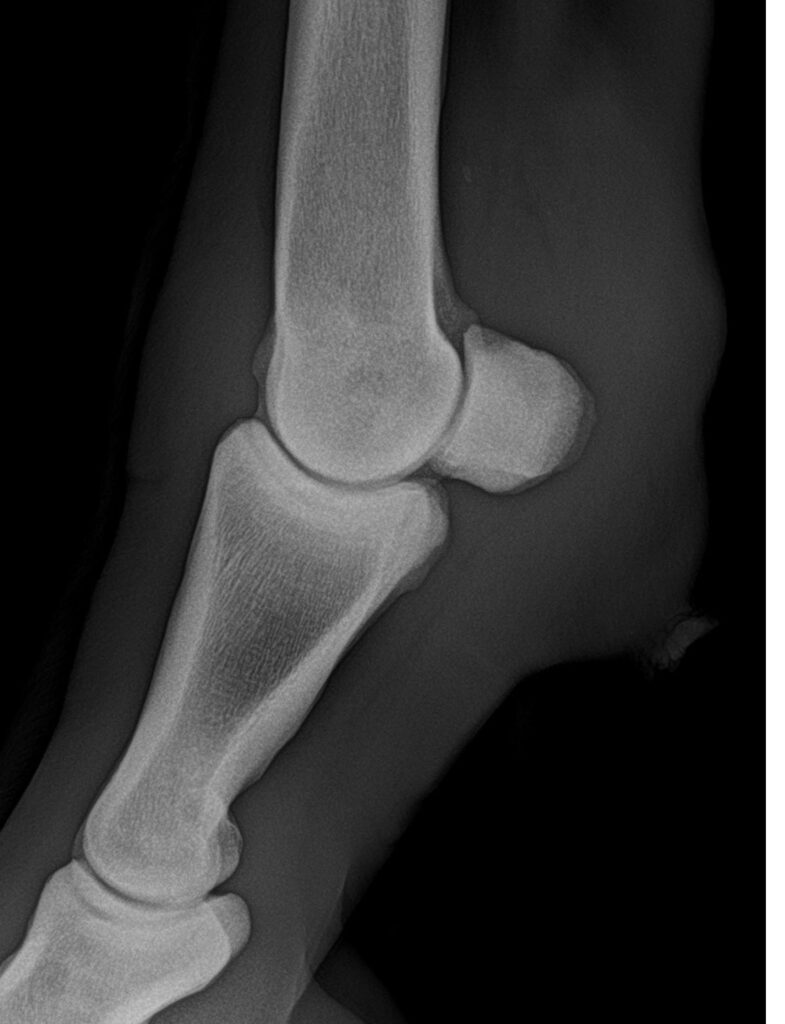

Orthopädie

Bildgebende Verfahren:

Ultraschall, Röntgen, JETZT auch Endoskopie